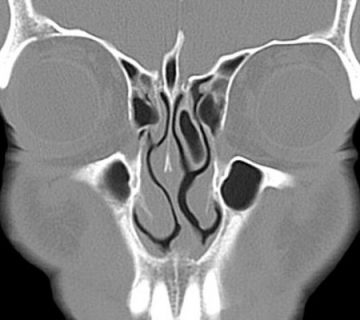

Para comprobar el estado general de los senos paranasales y extensión de las lesiones polipoideas, es usual solicitar la realización de una tomografía simple, con cortes axiales y coronales, de nariz y senos paranasales.